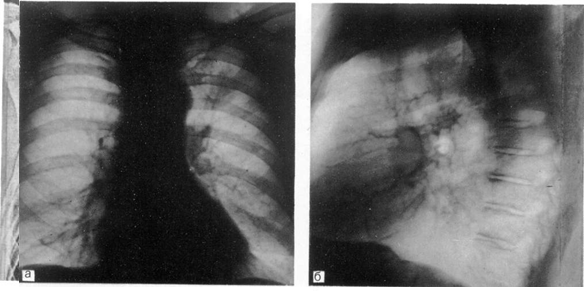

Бронхография легких может быть выполнена под наркозом. Особенность ее проведения заключается в том, что больной лежит на спине, осуществляется  искусственная вентиляция легких в условиях миорелаксации. Контрастное вещество вводят через интубационную трубку и в период кратковременного апноэ выполняют рентгенограммы обоих легких в прямой и косых проекциях (рис. 5).

Рис. 5. Поднаркозная бронхография у ребенка. Косая проекция. Норма.